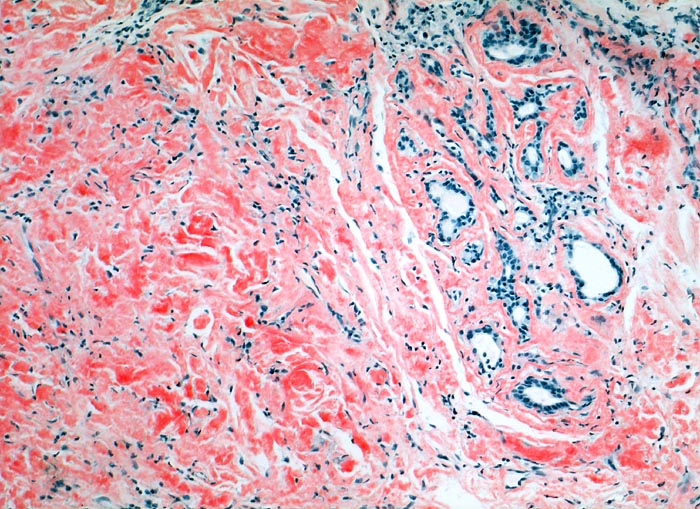

PathoPic – image database / PathoPic ID 4272 - Lokalisierte Amyloidose

Lokalisierte Amyloidose

Larynx

Massenhaft kongorote Amyloidablagerungen im Stroma.

Immunhistochemisch AL-Amyloid

Bei der laryngealen Amyloidose handelt es sich oftmals um eine lokalisierte Erkrankung ohne Systembeteiligung. Sie kann zu heiserer Stimme oder Dyspnoe führen. Meist handelt es sich wie im vorliegenden Fall um AL-Amyloid. Nach einer Systembeteiligung sollte klinisch gesucht werden.